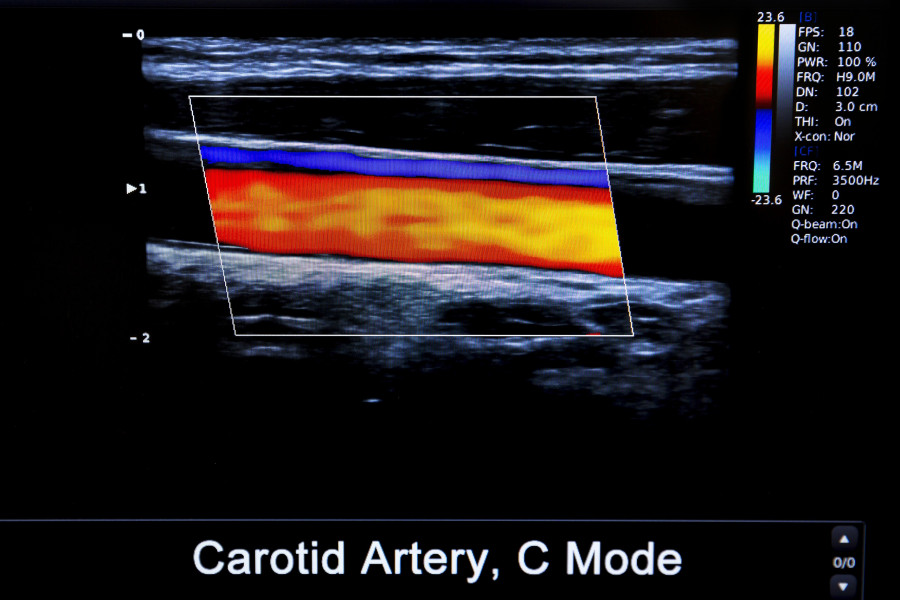

Colourful Image Of Modern Ultrasound Monitor

Πολύχρωμη απεικόνιση της καρωτίδας αρτηρίας μέσω ηπερήχων

Μια νέα μελέτη προσφέρει μια εκπληκτικά απλή προσέγγιση: ένα μη επεμβατικό υπερηχογράφημα του τραχήλου μπορεί να βοηθήσει στον εντοπισμό ανδρών με υψηλό κίνδυνο ανάπτυξης καρδιακής ανεπάρκειας πολύ πριν εμφανιστούν τα συμπτώματα.

Τα ευρήματα υποδηλώνουν ότι ανεπαίσθητες ανωμαλίες στην καρωτίδα αρτηρία (το κύριο αιμοφόρο αγγείο στον τραχήλο, που τροφοδοτεί με αίμα τον εγκέφαλο) μπορεί να αποκαλύψουν πολλά για την καρδιαγγειακή υγεία.

Οι ερευνητές χρησιμοποίησαν απεικόνιση υπερήχων για να μετρήσουν την ελαστικότητα της καρωτιδικής αρτηρίας, τη συσσώρευση πλάκας και άλλες αλλαγές στα αγγεία σε άνδρες χωρίς γνωστή καρδιακή νόσο. Στη συνέχεια, παρακολούθησαν τους συμμετέχοντες με την πάροδο του χρόνου, για να δουν ποιοι εκδήλωσαν εν τέλει καρδιακή ανεπάρκεια.